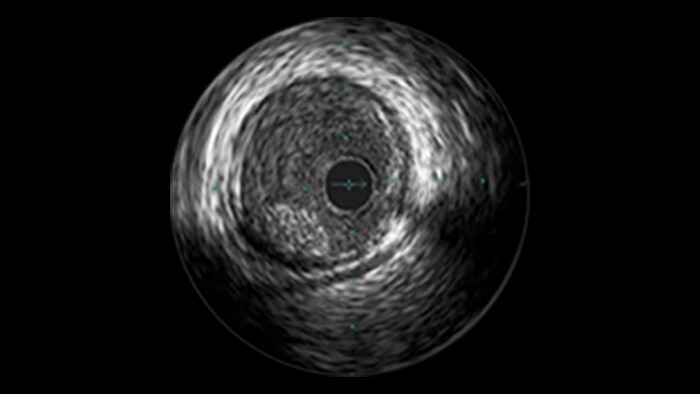

IVUS-guided vs. angiography-guided outcomes3